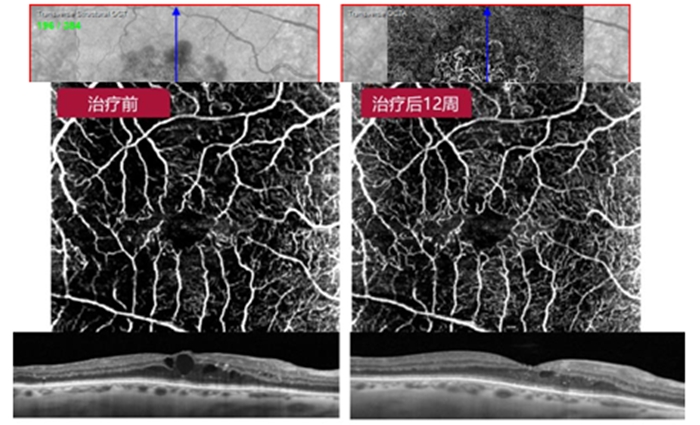

??? 二、OCT血管成像(OCTA)

??? OCT血管成像(OCTA)是一種無創(chuàng)、快速、分層顯示眼底視網膜及脈絡膜血管的嶄新科技,是目前最前沿的技術之一。主要應用于眼科各種疾病檢查,尤其眼底病的診斷,如黃斑變性、糖尿病性視網膜病變、視網膜靜脈阻塞、青光眼、高度近視等等疾病。相比傳統(tǒng)的眼底造影檢查有四大優(yōu)勢。

??? 3、精確分層,OCTA技術可以對視網膜及脈絡膜血管進行精細分層,充分彌補了傳統(tǒng)造影的不足;